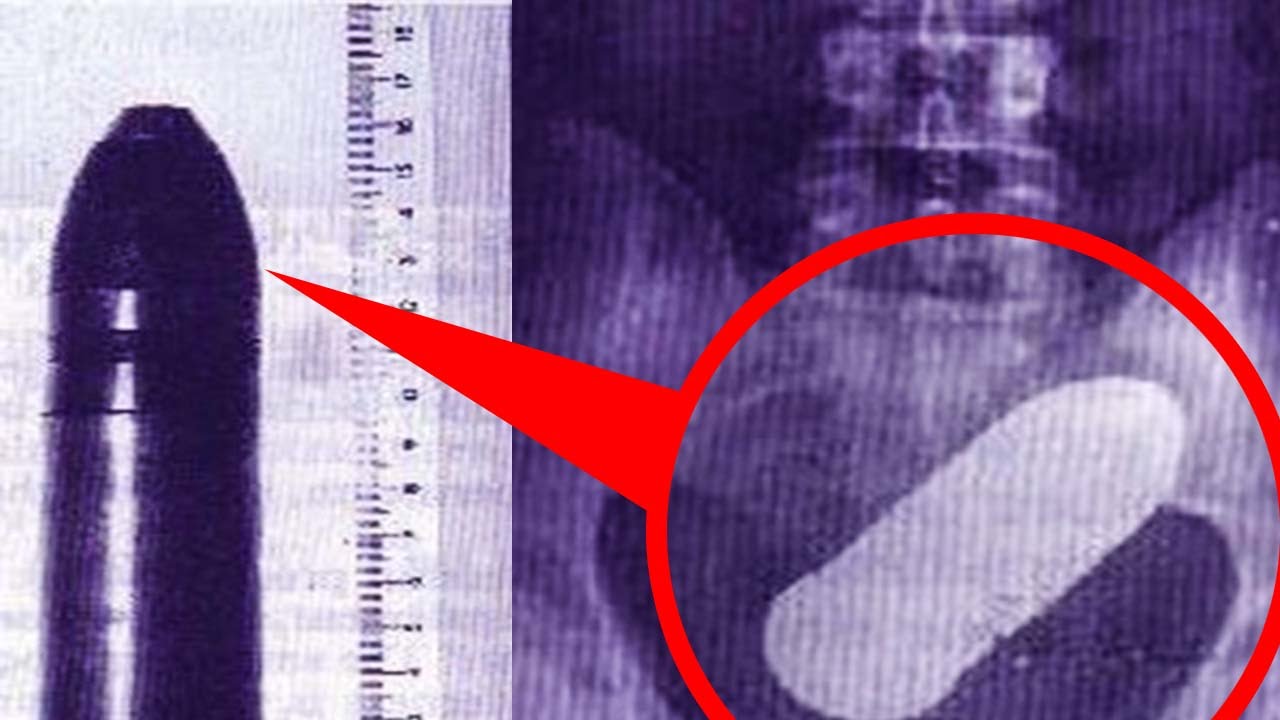

Врач может отыскать инородное тело в заднем проходе во время пальцевого исследования прямой кишки. Также инородные тела определяются путем рентгенологического исследования.

Для того, чтобы выяснить, повреждена или нет стенка толстой кишки, проводится инструментальное обследование — ректороманоскопия и рентгенография (ирригоскопия).

Затем может потребоваться обследование с помощью ректоскопа, а также рентген брюшной полости для определения точного расположения инородного предмета.